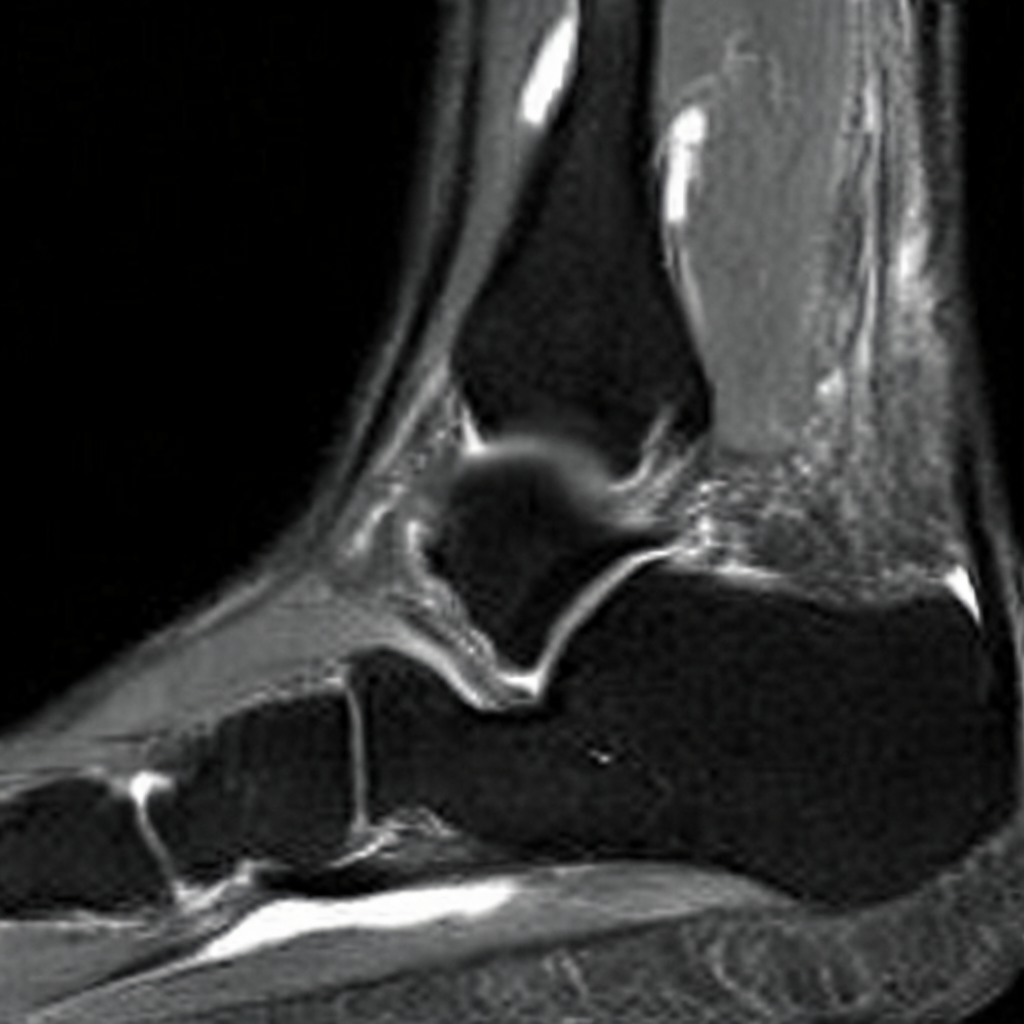

Diffusion models have recently gained significant traction due to their ability to generate high-fidelity and diverse images and videos conditioned on text prompts. In medicine, this application promises to address the critical challenge of data scarcity, a consequence of barriers in data sharing, stringent patient privacy regulations, and disparities in patient population and demographics. By generating realistic and varying medical 2D and 3D images, these models offer a rich, privacy-respecting resource for algorithmic training and research. To this end, we introduce MediSyn, a pair of instruction-tuned text-guided latent diffusion models with the ability to generate high-fidelity and diverse medical 2D and 3D images across specialties and modalities. Through established metrics, we show significant improvement in broad medical image and video synthesis guided by text prompts.

In this work, we focus on the ability of LDMs to generate novel datasets to overcome class imbalances traditionally associated with medical data, and potentially reduce the need for manual annotation of medical 2D and 3D data. We present MediSyn, a pair of text-guided latent diffusion models for broad medical 2D and 3D modality synthesis. To overcome the scarcity of labelled medical data, we leverage a vast corpus of more than 5 million image-caption pairs and 100,000 video-caption pairs collected from the public domain across numerous medical specialties, and integrate comprehensive natural language annotations to develop a pair of versatile diffusion models for the medical domain.

Since their introduction, generative models have had a rich history in the medical field, ranging from anomaly detection and image denoising [21, 22], to image reconstruction and segmentation [23, 24]. For instance, DDPMs have been trained to convert MRIs to CTs for soft tissue injury [25], synthesize labeled brain MRIs for training segmentation models [26], denoise OCTs to erase visual artifacts [27], and reconstruct images for accelerated MRI scans [28].

Our findings demonstrate Medisyn’s remarkable ability to generate high-fidelity and diverse medical images, image sequences and volumetric scans across various medical subspecialties and imaging modalities. Other medical text-driven diffusion models, such as TauPETGen [42] for tau PET images and GenerateCT [43] for chest CT volumes, have proven successful in generating high-quality images that accurately depict anatomical features and clinical conditions. However, these models are constrained to a single imaging modality and anatomical region, thereby restricting their applicability. Moreover, they were trained on relatively small datasets sourced from a limited number of institutions, which could lead to more biased outputs. In contrast, Medisyn, having been trained on one of the largest publicly accessible medical image and video datasets to date, is equipped to synthesize data that cover numerous medical disciplines, population groups, and disease states. Leveraging our two models, we can synthesize new medical datasets as well as augment existing ones, potentially improving a wide array of medical machine learning tools, both general and specialized. Additionally, our models can minimize the need to repeatedly fine-tune on specific datasets for generating different imaging modalities, thus reducing computational costs for academic labs.